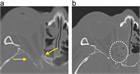

1. 造影CT(CTAngio)検査についてテキスト、画像を追加した。

1. 治療法に関し、ステロイドの投与、外科的視神経減圧術ついてテキスト、画像を追加した。